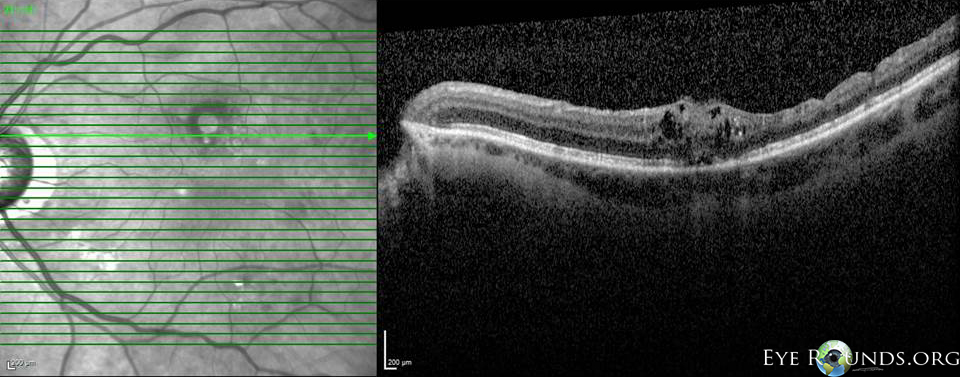

Fig 3-8: OCT OS: scant ERM remnants nasal to the fovea; thinning temporal in areas of prior membrane peeling.